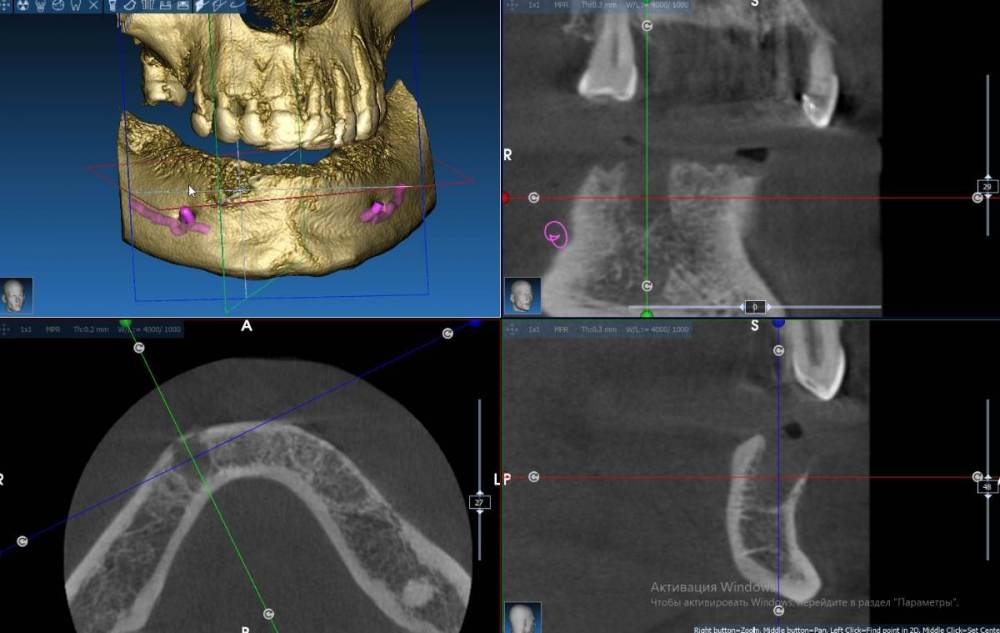

Fin Опубликовано 13 марта, 2022 Поделиться Опубликовано 13 марта, 2022 Здравствуйте коллеги. Появился очень странный вопрос. Год назад у меня был пациент - мужчина 40 лет на консультацию по имплантации все на 6 на НЧ. В процессе осмотра снимка КТ обнаружил в зоне 43 хронический воспалительный процесс. Данный процесс был прокюретажен, пациент отпущен на заживление на пару месяцев. Старый снимок Так получилось что с пациентом мы встретились только сейчас и решили продолжить наше лечение. Далее повторное КТ со скан маркерами на его съемном протезе, сделан слепок протеза- пациент отпущен. В ходе планирования шаблона я обнаружил улучшение со стороны воспалительного процесса но так же обнаружил странное образование рядом не сообщающееся со старым воспалением. Новый снимок Подскажите что это может быть т.к. вижу такое впервые. Сам думаю что скорее всего я преувеличиваю и это из-за того, что снимки сделаны на разных аппаратах, но хотелось бы услашать Ваше мнение. Ссылка на комментарий

Doctor Vlad Опубликовано 14 марта, 2022 Поделиться Опубликовано 14 марта, 2022 кортикалки то не стало в стороне от лунки. может и стоит Ссылка на комментарий

Женька Опубликовано 28 марта, 2022 Поделиться Опубликовано 28 марта, 2022 @syrovovec вот этот участок вас не смутил? 1 Ссылка на комментарий